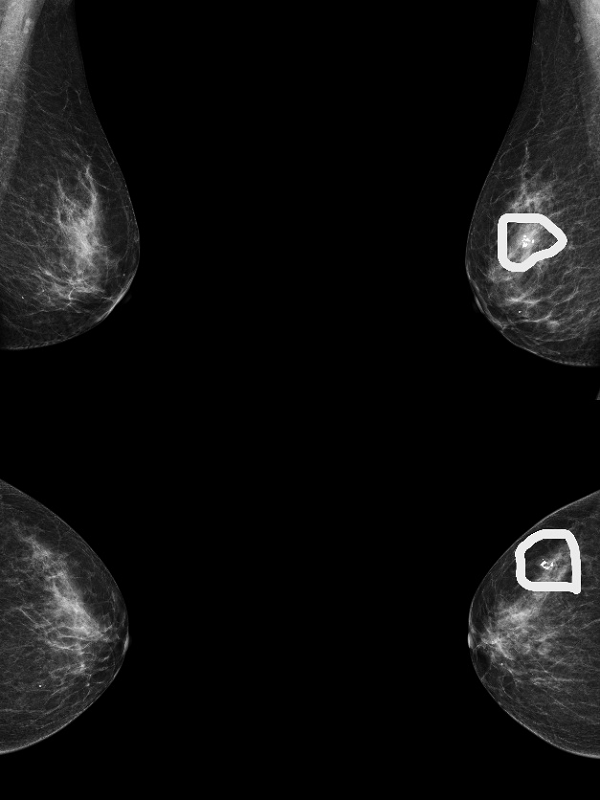

患者B钼靶检出多发钙化灶,超声虽未显示钙化,但发现了钼靶未显示的实性结节(如图3、4)。

图3 患者B的钼靶图像,显示乳腺多发钙化灶(图中画圈处)